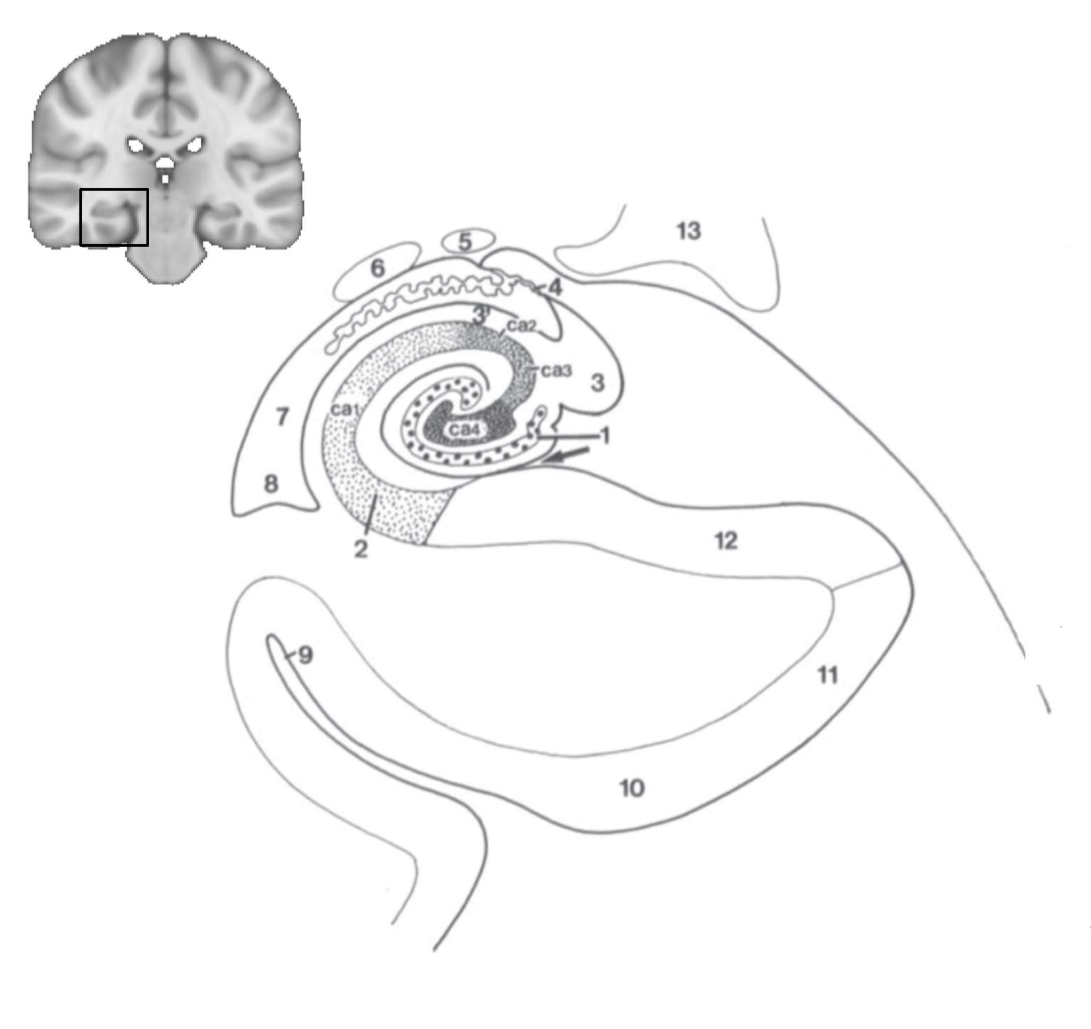

What structure is this?

hippocampus

What is 1?

hippocampus

What is 2?

rhinal sulcus

What is 3?

lateral ventricle

What is 4?

thalamus

What is 5?

entorhinal cortex

What is 6?

perirhinal cortex

What is 7?

parahippocampal cortex

What is 1?

gyrus dentatus

What is 2?

cornu ammonis

What is 3?

fimbria

What is 3’?

alveus

What is the arrow pointing to?

happicampal sulcus

What is ca1, ca2, ca3 and ca4?

fields of cornu ammonis

What is 4?

tela choroidea

What is 5?

stria terminalis

What is 6?

tail of caudate nucleus

What is 7?

temporal horn of lateral ventricle

What is 8?

collateral eminence

What is 9?

collateral sulcus

What is 10?

parahippocampal

What is 11?

entorhinal area

What is 12?

subiculum

What is 13?

lateral geniculate body